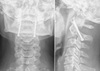

Grading of atlantoaxial rotatory subluxation?

A

Fielding and Hawkins:

I: rotation without anterior displacement of C1

- transverse ligament intact

II: rotation with 3-5mm of C1 anterior displacement

- transverse ligament damaged

III: rotation with >5mm of C1 anterior displacement

IV: posterior displacement of C2

- rare, in rheumatoid